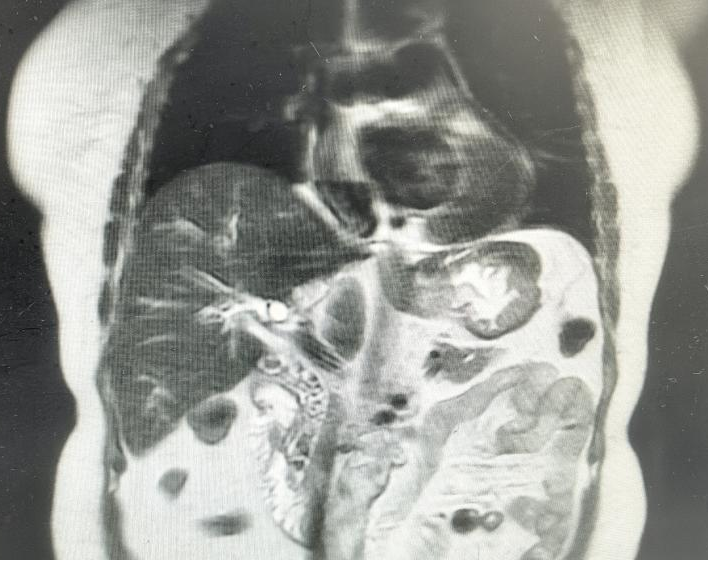

术前磁共振显示

主刀医生沿右肋缘做了个切口、逐层切开入腹探查——胆总管囊状扩张,结石像一座微型石林,层层叠叠卡在胆总管及肝内胆管,有的已经跟胆管壁长在一起,左半肝部分纤维化萎缩。团队果断进行手术:左半肝直接切除,这叫解剖性肝叶切除,沿肝脏天然分界线精准切割,该留的一寸不多切,该去的毫不含糊;胆囊一并拿掉;接着进行胆总管探查取石,随着取石钳将结石一颗一颗清理干净,术中探测oddi括约肌失能,于是同时行胆肠内引流,胆总管与空肠吻合改道手术,最后T管引流。

术后带气管导管送入医院重症医学科(ICU病房)接受精心治疗,密切观察生命体征平稳后再转回肝胆外科病房继续治疗。

让人欣慰的是,奉老太恢复得比预想快得多。科室全面推行的ERAS加速康复方案起了作用:术后尽早下床、尽早进食、优化镇痛,让患者少遭罪、早出院。